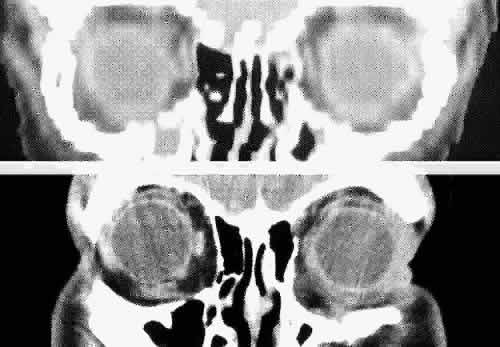

Fig. 4. Comparison of a direct coronal computed tomography scan at the level of midglobe (inferior) and coronal multiplanar reconstructions at the same level (superior).

Direct multiplanar CT imaging provides a much improved image over those obtained through multiplanar reconstruction (Fig. 4). This technique is “slice-oriented” in that each image is obtained directly by scanning in a plane perpendicular to the tissue slice whose image is desired. In contrast, multiplanar reconstruction is “volume-oriented” in that the reconstructed images are based on the total volume of tissue imaged in one particular, usually axial, plane. Direct coronal and sagittal CT scanning requires special patient positioning that may not be possible for all patients.1,5,6,15 However, the images produced by direct scanning have significantly higher spatial resolution and quality than those produced by multiplanar reconstruction. In addition, such direct scans avoid imaging artifacts caused by eyelid and ocular movement that often occur in imaging by multiplanar reconstruction. On the other hand, imaging artifacts caused by dental appliances are often present on direct coronal and sagittal scanning. Generally, direct coronal scanning should be obtained, whenever possible, to supplement axial orbital scans to image this area most accurately (Fig. 5). Direct multiplanar imaging of the orbit and optic nerve is particularly helpful in instances of ocular and orbital trauma and in cases in which evaluation of the extraocular muscles, optic nerve, chiasm, canal, and perisellar or cavernous sinus areas is desired.